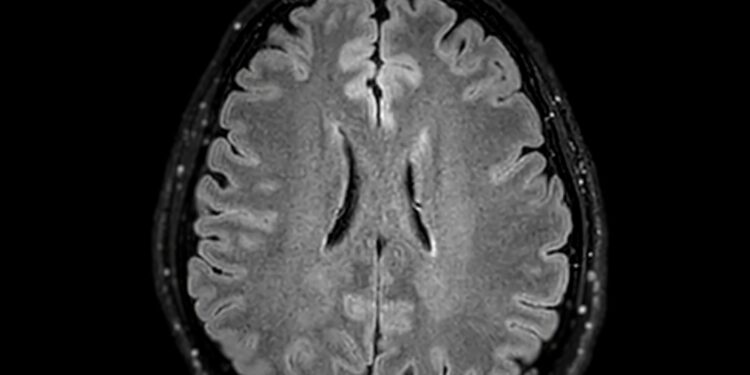

- Vaizdiniai tyrimai, pavyzdžiui, magnetinio rezonanso tomografija (MRT)